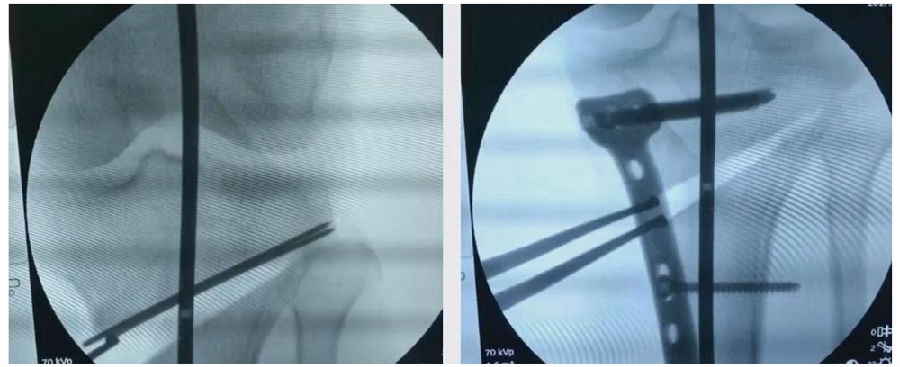

(3)拉力钉技术

第3个原因和拉力钉使用技术有关。拉力螺钉的使用是希望在合页端产生一个加压的效果,如果拉力螺钉使用过度,会出现合页端拉断的情况,导致Ⅱ型骨折。所以要求拉力螺钉在使用时加压不要过度,通常当钢板有轻微的变形即可,不要过度加压。

因为外侧合页周围有软组织,即使是说骨性合页断了,但是由于软组织合页还在,所以只要用拉力螺钉复位固定,维持好力线即可。术后患者正常康复,预后较好。